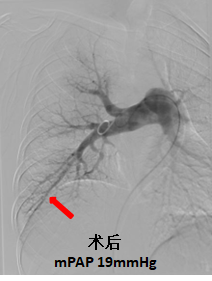

慢性血栓栓塞性肺动脉高压患者肺动脉残余血栓堵塞部分血管引起肺动脉高压,应用球囊扩张手术治疗可以明显改善被堵塞血管的血流,降低肺动脉压力,大部分患者胸闷气短症状完全改善,甚至可以恢复正常生活。